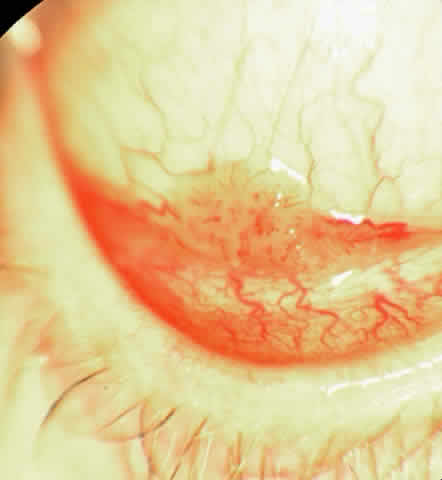

In the conjunctiva, HPV can induce papillomatous lesions (papillomas and inverted papillomas) and epithelial dysplastic lesions consisting of conjunctival intraepithelial neoplasia and squamous cell carcinoma. Conjunctival papillomas were traditionally divided into infectious, limbal, and inverted types; however, current data suggest that all types have a viral etiology. All sites of the conjunctiva can be affected, and involvement of the contiguous epithelium of the lacrimal canaliculus, lacrimal sac, and nasolacrimal duct has been noted to occur.38,61,62 Conjunctival papillomas can be pedunculated or sessile and are typically shiny, flesh-colored, and papillomatous (Fig. 1). Each papillary frond has a vascular core that is easily seen through the nonkeratinized epithelium. The papillomatosis is responsible for the typical appearance of evenly spaced vessels throughout the lesion. If keratinized, these lesions may appear whitish and dull. Papillomas can be either unilateral or bilateral, and they can be either solitary or multifocal (Fig. 2). Inverted papillomas are the least common type of papilloma in all sites, but they constitute a larger portion of lacrimal sac tumors than other periocular tumors.63,64

The epithelial dysplastic lesions—conjunctival intraepithelial neoplasia and squamous cell carcinoma—almost always begin at the limbus, most commonly in the interpalpebral zone.57,58 The initial appearance is a gelatinous, gray lesion with some thickening (Fig. 3). There may be increased vascularization. The epithelial changes may extend onto the cornea, causing a hazy, gray appearance. Tumor vascularity lags behind the lead margin of the epithelial change. As the lesions progress from dysplastic to carcinomatous, they become thicker, more vascularized and may show keratinization, giving a leukoplakic appearance (Fig. 4). Lesions confined to the epithelium move freely over the sclera, whereas invasive lesions are fixed to underlying tissue. Occasionally squamous cell carcinomas appear identical to classic papillomas.